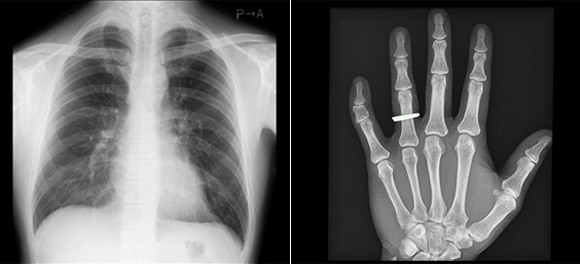

レントゲン検査

当院のレントゲン装置はKonica社製AeroDR fineのフラットパネルを使用しています。分解能が100μmと非常に高画質な画像を提供出来ます。 レントゲン検査は放射線を使用しますが、必要最低限の放射線量を使用しています。しかし、妊娠の可能性がある方はリスクが高い為、スタッフへご相談ください。